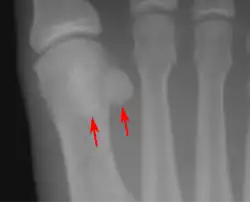

• One or both of the sesamoid bones under the first metatarsophalangeal joint (of the great toe) can be multipartite – in two or three parts (mostly bipartite – in two parts).[11]